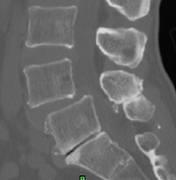

近日,市四医院脊柱创伤外科手术团队在全市较早将微创经椎间孔腰椎椎体融合技术(misTLIF)用于腰椎管狭窄症和腰椎滑脱症患者。手术为经皮微创置钉,在通道下行神经减压椎体复位及椎间融合,手术切口仅有几厘米,手术创伤小,患者术后次日可下床。完成该手术的两名患者腰腿痛症状缓解,手术取得明显成效。

据悉,腰椎管狭窄症是指各种原因引起椎管变窄,压迫硬膜囊、脊髓或神经根,从而导致相应神经功能障碍的一类疾病。腰椎滑脱症是指某个腰椎的椎体相对与邻近的腰椎向前滑移,即为腰椎滑脱,它们是导致腰痛及腰腿痛等常见腰椎病的病因之一,多发于40岁以上的中年人。随着现代生活习惯、节奏的改变,腰椎退变所致的腰椎管狭窄症和腰椎滑脱症患者越来越多,严重威胁广大患者的生活质量。

misTLIF手术是近年来发展起来的一项骨科新技术,主要用于腰椎管狭窄症、腰椎滑脱症。它与传统的开放手术相比,有着明显优势,术中切口小,创伤出血少,且无需广泛切开肌肉韧带等软组织,避免了因肌肉软组织剥离过多而导致的迟发性脊柱不稳;由于手术创伤小,术后患者恢复快,可以尽早下床活动,减少了术后切口感染以及卧床时间过长带来的一系列并发症。